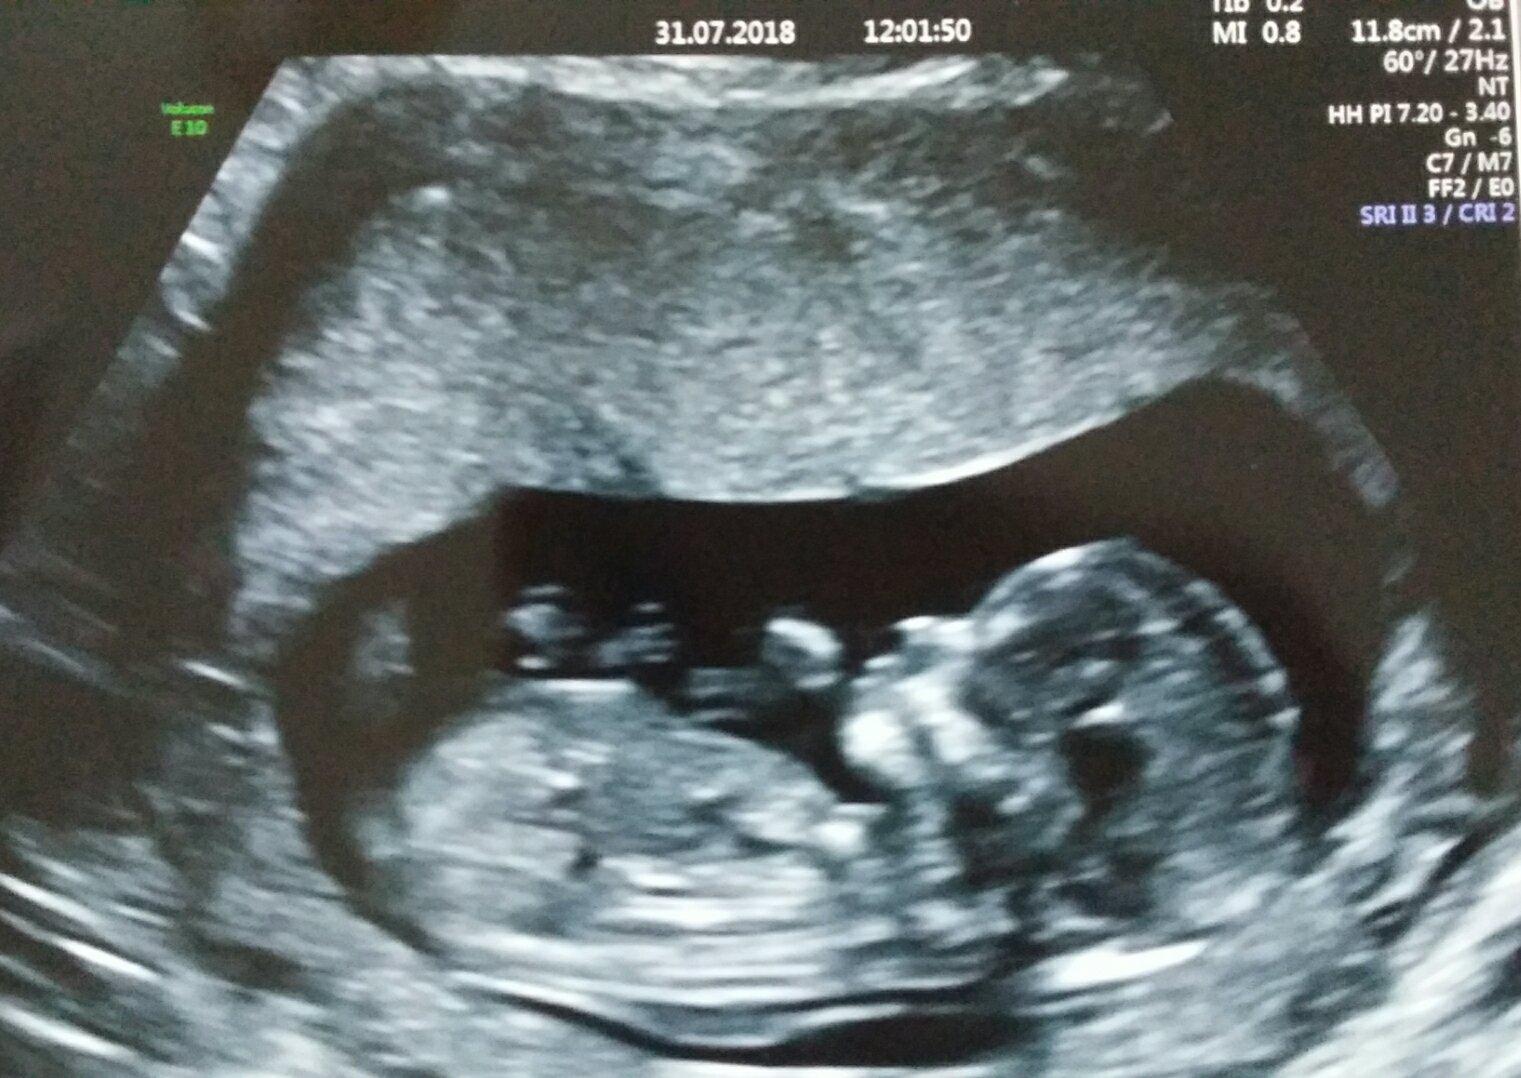

@lenkatorka to je husta fotka 😍 , gratuluju, to uz je normalni clovicek ❤

@skretik taky jsem si říkala ,ze to už je člověk ❤

@lenkatorka ja jdu zitra, tak jsem taky zvedava, co uvidime a jestli bude vse v poradku, snad se mi tam to mimi neupeklo :D

Ahoj holky, rada bych se k Vam take pridala 🙂 termin mam 21.2.2019...muzu se zeptat, kam jdete na prvotrimestralni screening? Ja se chystam ve ctvrtek do Gennetu na krev a pak jsem objenana 15.8. na UTZ 🙂 trochu se toho bojim, nemate nekdo s Gennetem zkusenosti, jal dlouho trva nez reknou vysledky, a co vsechno vlastne v te krvi zjistuji? Predem dekuji za odpoved 🙂

@jenssy Ja jdu taky do Gennetu. Byla jsem i se synem. Jsou tam peclivi. První ti naberu krev ke screening a pak jdeš za nějakou dobu na ten utz. Výsledky ti řekne dr až po UTZ jakmile spojí výsledky krve a utz dohromady v počítači. Samotná krev nic nevypovídá 🙂 zjišťují se vývojové vady.